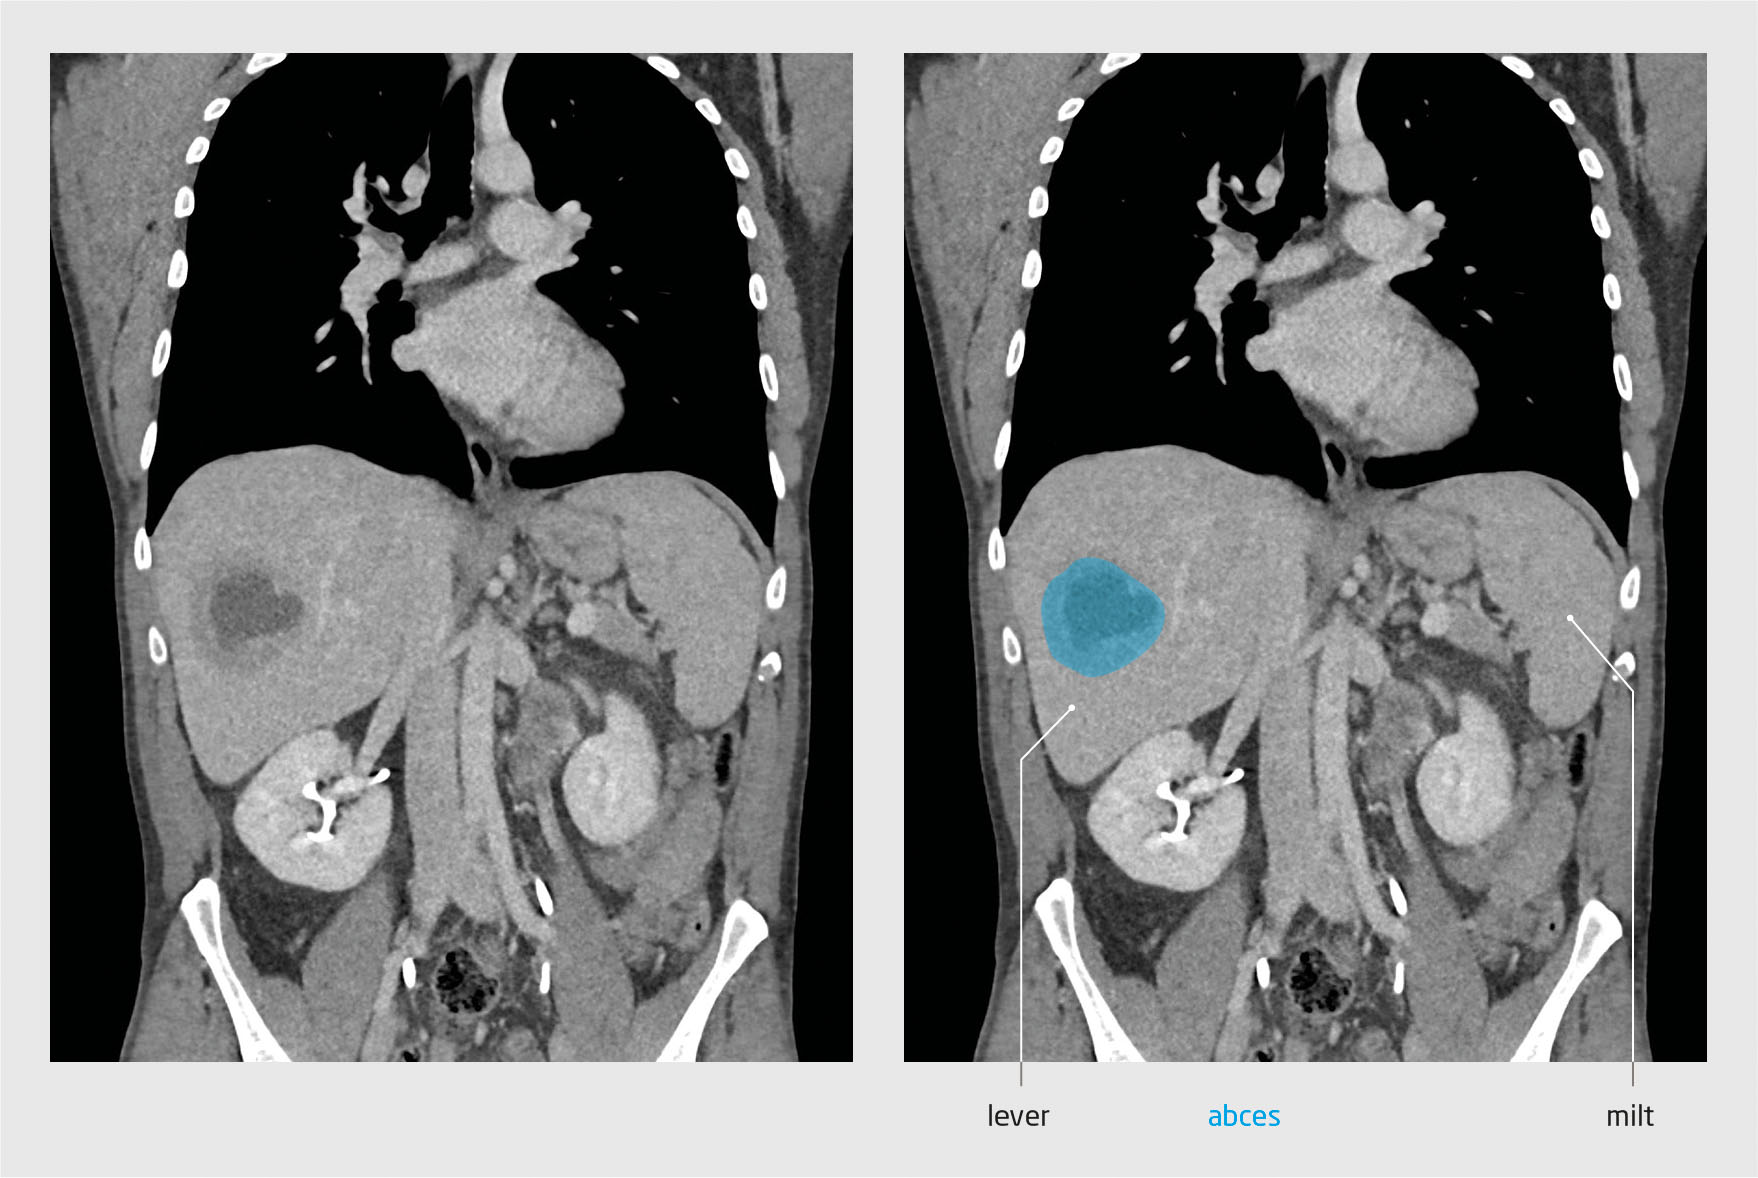

Patiënt A, een 46-jarige man met blanco voorgeschiedenis, meldde zich op de Spoedeisende Hulp met koorts, koude rillingen en dyspneu sinds 3 dagen. Bloedonderzoek toonde verhoogde leverenzymwaarden en sterk verhoogde infectieparameters. Er werden bloedkweken afgenomen. Op de X-thorax werd een mogelijk infiltraat in de rechter hilus gezien. Patiënt kreeg amoxicilline voorgeschreven bij de werkdiagnose ‘pneumonie’ en ging weer naar huis. De bloedkweek toonde 3 dagen later Fusobacterium necrophorum aan. Daarop werd patiënt opgenomen. Er werd een CT-hals/thorax/abdomen verricht, dat een leverabces met een diameter van ongeveer 5,7 cm toonde (figuur 1). De CT toonde geen tromboflebitis in de V. jugularis interna. Bij navraag bleek dat de patiënt 3 maanden eerder een wortelkanaalbehandeling had ondergaan, wat mogelijk de bron was voor het leverabces. De diagnose werd bijgesteld naar pyogeen leverabces, mogelijk syndroom van Lemierre. De patiënt werd behandeld met intraveneus cefuroxim en metronidazol. Het leverabces werd gedraineerd middels echogeleide punctie en uit het drainagevocht werd eveneens Fusobacterium necrophorum gekweekt.

Vanwege de verdenking op een maligniteit werd CT verricht. De CT-scan toonde een leverabces in leversegment V (figuur 2). Daarop vond drainage van het abces door echogeleide punctie plaats. Kweek van drainagevocht toonde een Fusobacterium nucleatum aan . De behandeling bestond uit intraveneuze toediening van ceftazidim en metronidazol. Bij navraag bleek de patiënt 4 maanden eerder een kiesextractie te hebben ondergaan, wat de bron van de infectie geweest zou kunnen zijn.